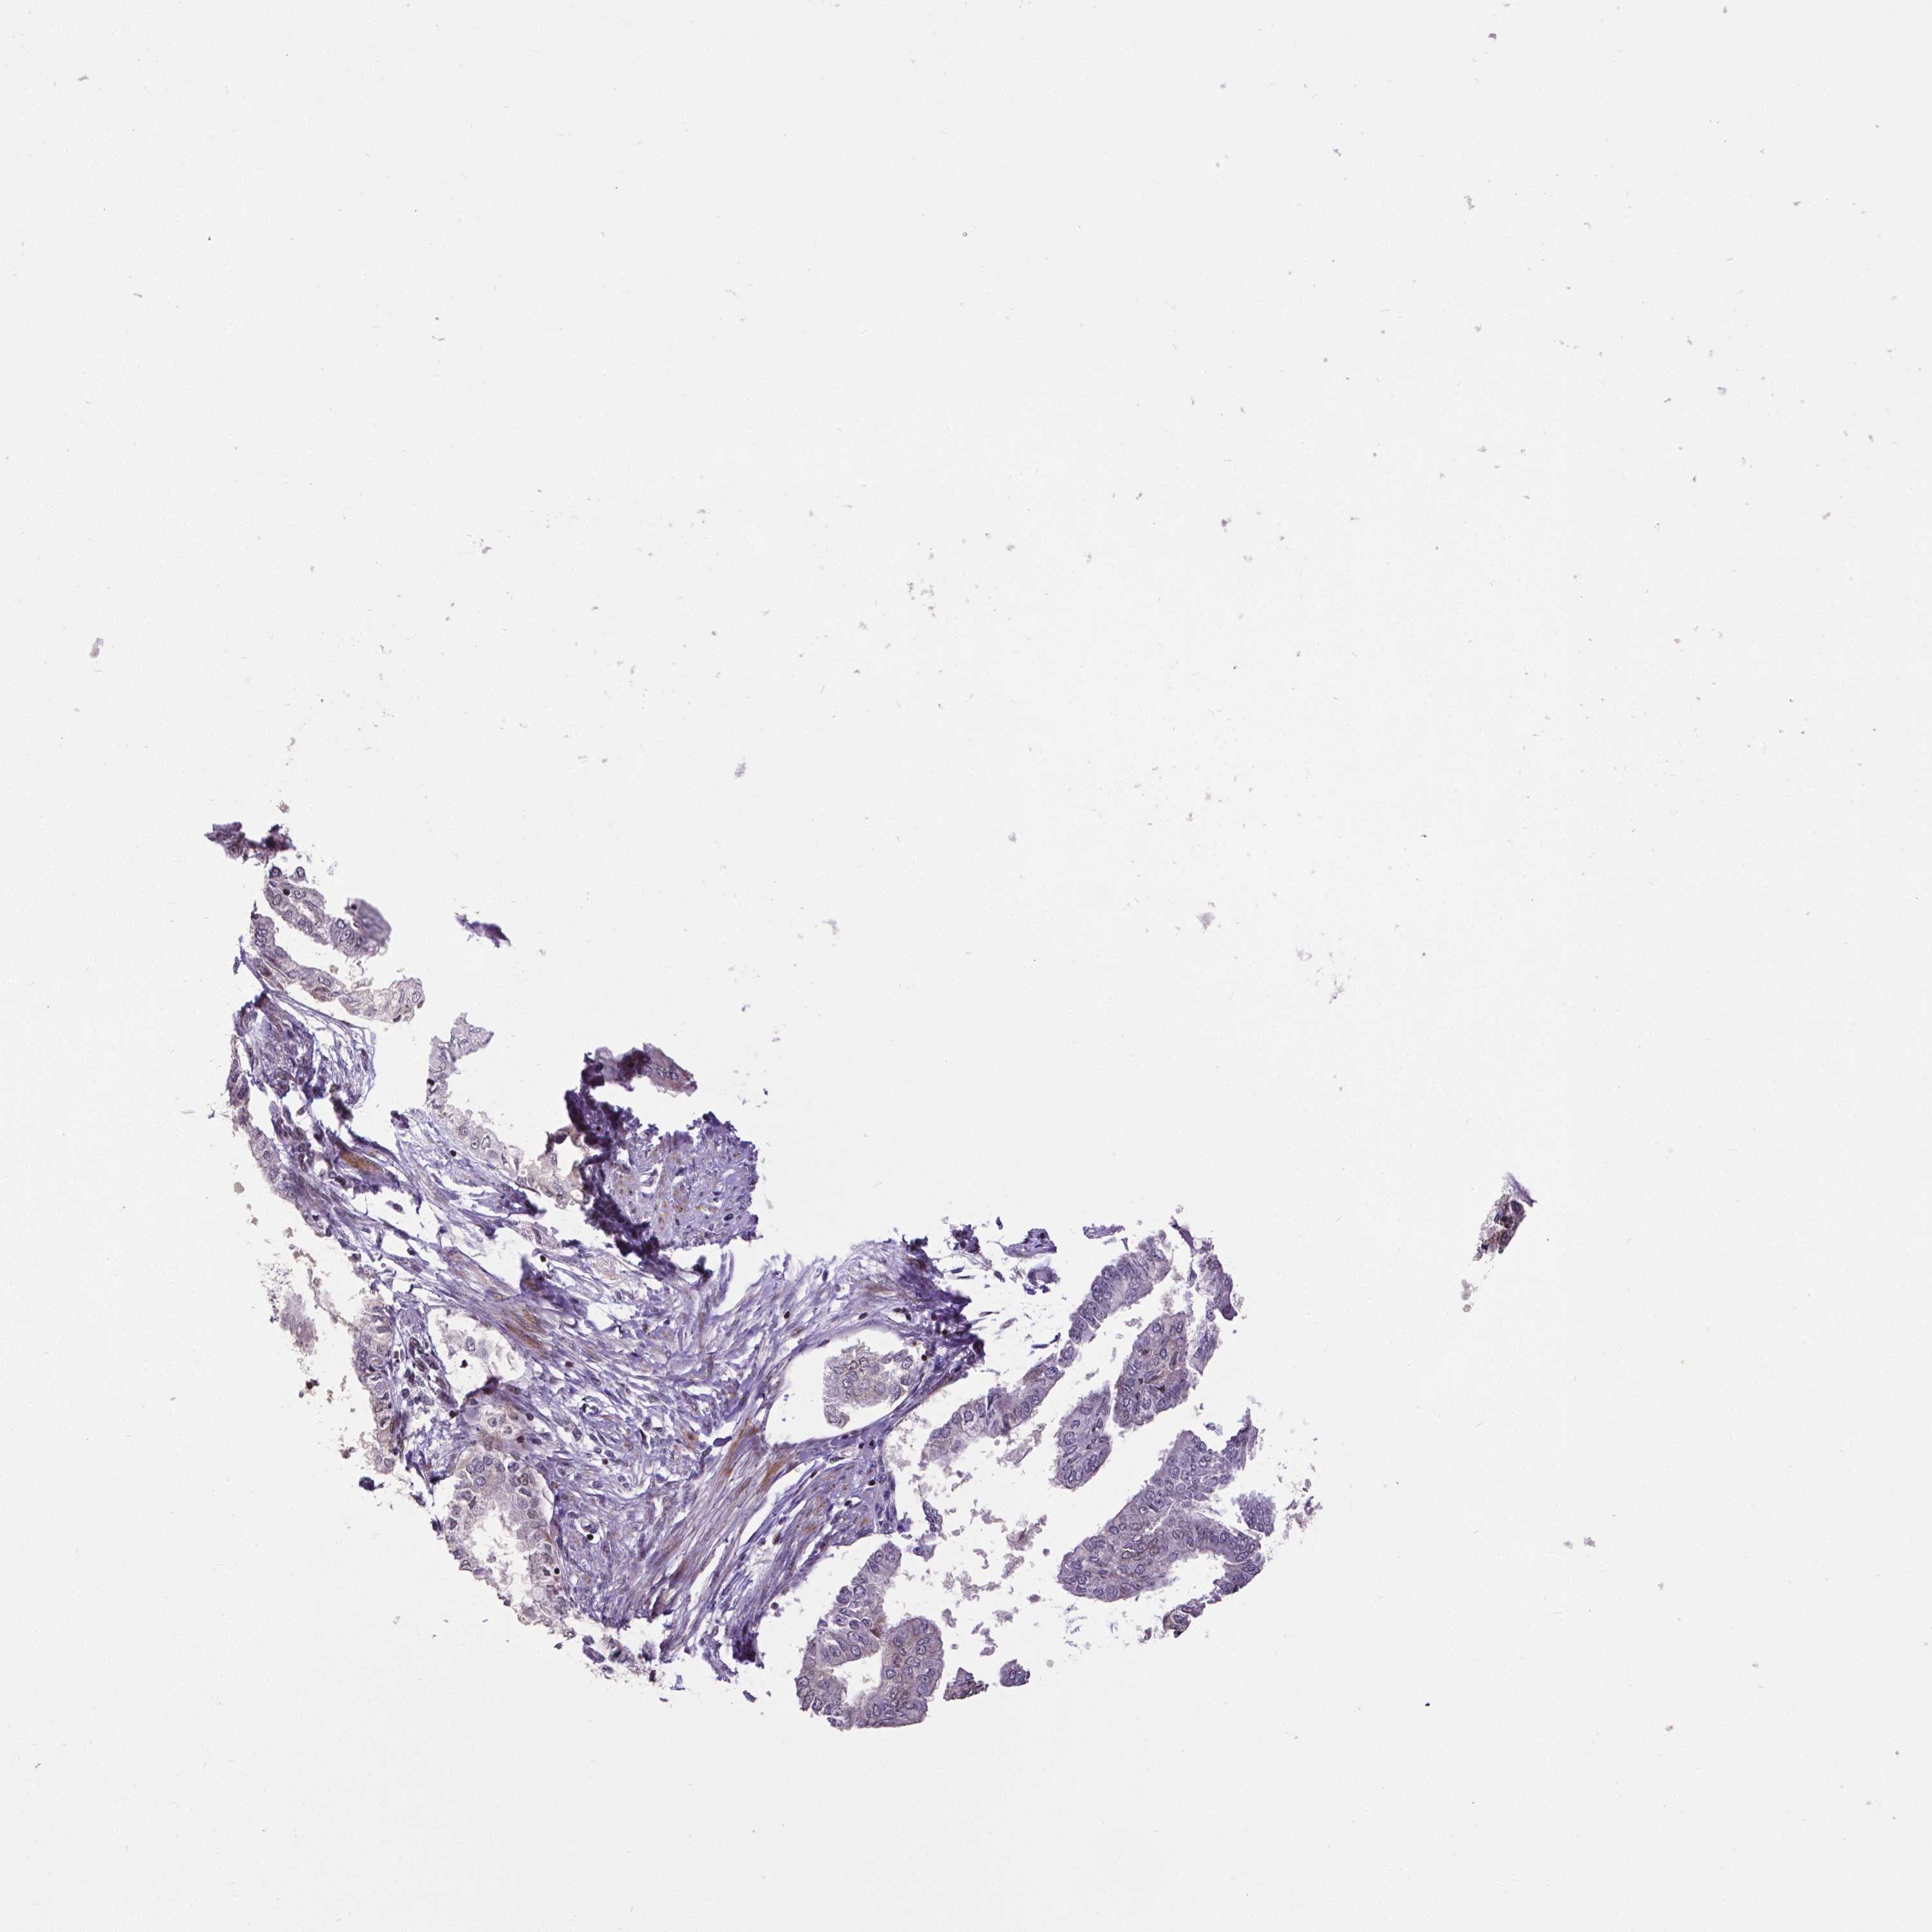

ENDOMETRIAL CANCER - Protein expressioni

A mouse-over function shows sample information and annotation data. Click on an image to view it in a full screen mode. Samples can be filtered based on level of antibody staining by selecting one or several of the following categories: high, medium, low and not detected. The assay and annotation is described here.

Note that samples used for immunohistochemistry by the Human Protein Atlas do not correspond to samples in the TCGA dataset.

Antibody stainingi

Antibody staining in the annotated cell types in the current human tissue is reported as not detected, low, medium, or high, based on conventional immunohistochemistry profiling in selected tissues. This score is based on the combination of the staining intensity and fraction of stained cells.

Each image is clickable and will lead to virtual microscopy that enables deeper exploration of all samples and also displays staining intensity scores, fraction scores and subcellular localization as well as patient and tissue information for each sample.

Antibody CAB068182